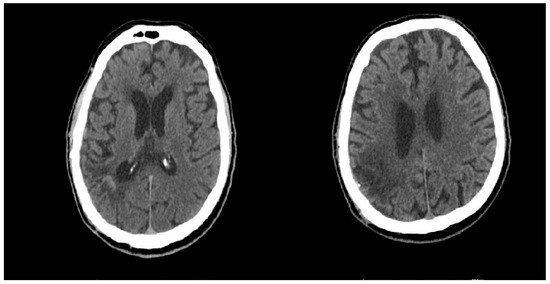

4.2. First Admission

4.3. Second Admission